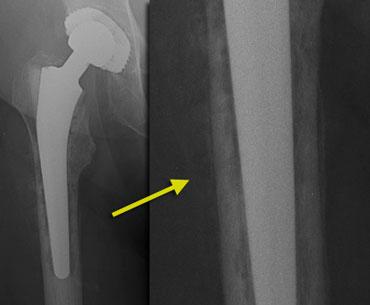

Gãy xương quanh khớp nhân tạo

Gãy xương có thể xảy ra sau phẫu thuật ở những bệnh nhân có chất lượng xương kém và sử dụng khớp nhân tạo thay thế có cán dài, hoặc khi giải phẫu bất thường như trong trường hợp loạn sản khớp háng hoặc đã từng phẫu thuật trước đó.

Gãy xương cũng phổ biến hơn với các cán xương đùi không xi măng, vì các loại này phải vừa khít chính xác và có thể gây gãy xương trong quá trình đặt khớp.

Tỷ lệ gãy xương dao động từ 0,1 đến 1,0 phần trăm đối với các thành phần có xi măng và từ 3 đến 18 phần trăm đối với các thành phần không xi măng. Hầu hết các trường hợp gãy xương trong phẫu thuật xảy ra ở phía xương đùi.